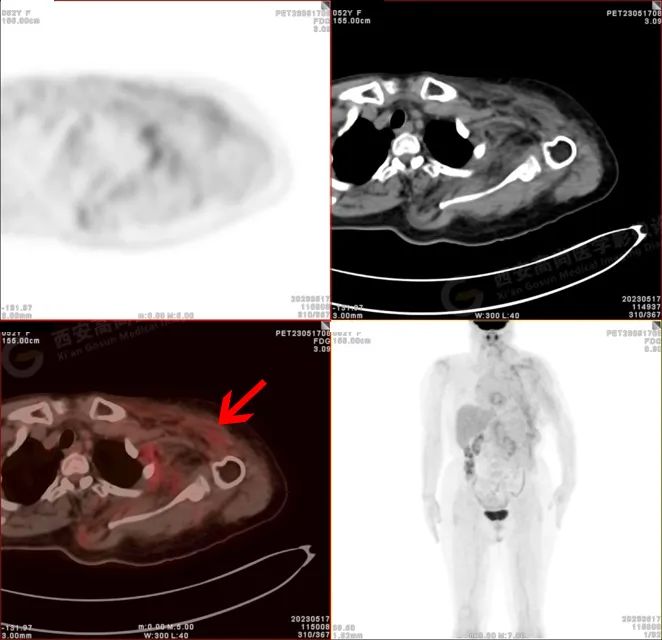

PET/CT 影像图

检查所见

左侧上臂、颈 4-腰 4 椎体水平左侧颈、左侧肩部、左侧腋窝、左侧胸部(含左侧乳腺)、左侧腹部、左侧背部广泛区域皮下及肌肉区可见疏松、肿胀混杂密度软组织病变,边界模糊不清,相邻骨质结构完整,上述病变呈不均匀放射性摄取轻度异常增高,SUV 最大值介于 1.2-2.4。上述改变,符合韧带样纤维瘤病。